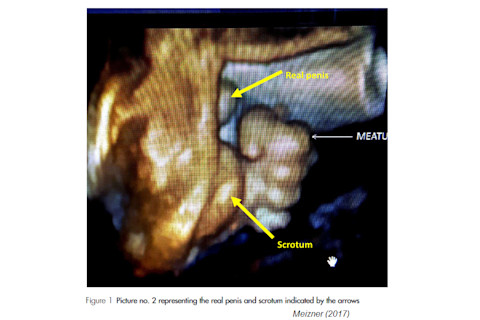

Looking at Figure 1 presented in the letter, one would have to conclude that the authors have made one huge error in the interpretation of the pictures presented. Picture no. 1 in Figure 1 represents a grasped normal hand with five fingers. What the authors mark as foreskin is the normal index finger. In picture no. 2 in Figure 1, one can see the flexed hand with five fingers. What the authors mark as meatus is the flexed index finger, a bit drawn backwards. The normal penis and scrotum are clearly visible in this picture, appearing medially to the clenched hand. I have indicated real penile tip and scrotum on a photocopy of picture 2, enclosed herewith.

Meizner included a (rather grainy) figure with what he says is the "Real Penis" helpfully labelled in yellow - and it's not in the fetus's hand: